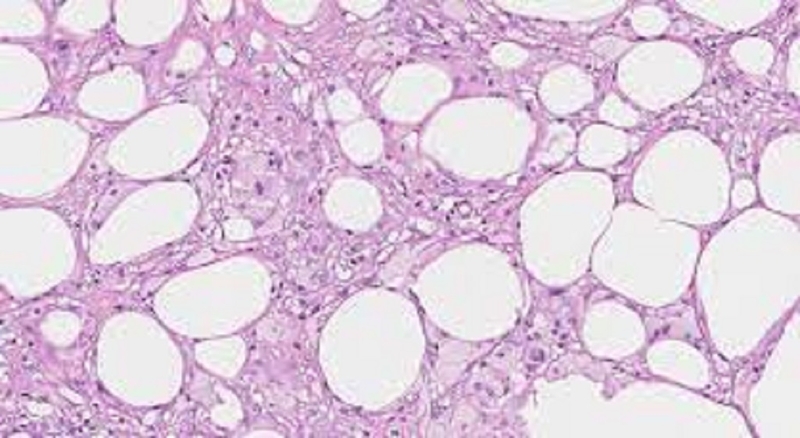

• Thoái hoá mỡ (Lipoic Degeneration): Là trạng thái khi giọt mỡ xuất hiện trong bào tương tế bào. Biểu hiện của thoái hoá mỡ là sự hiện diện của những hốc sáng lớn, tròn đều trong bào tương tế bào khi nhuộm bằng H.E. Thường gặp ở tế bào gan, đặc biệt là vùng trung tâm tiểu thuỳ, là kết quả của các rối loạn chuyển hóa như nghiện rượu hoặc sau viêm gan.